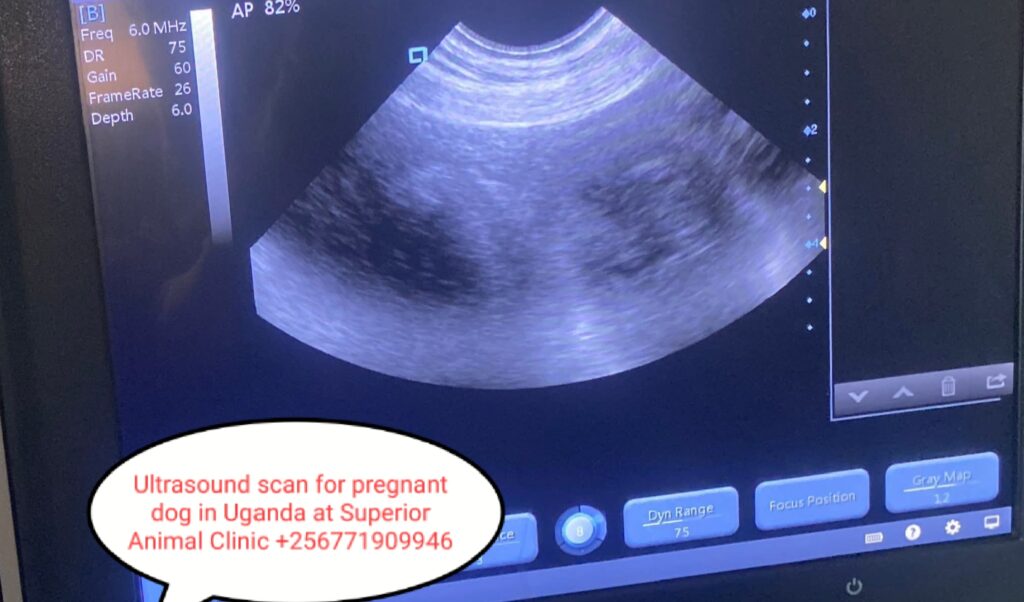

- Key weeks to watch: days 25–35 (ultrasound reliable), day 45+ (X-ray to count pups), final 2 weeks—rapid fetal growth and nesting.

- Ultrasound: from about day 25–30 after mating. Best for confirming pregnancy and checking fetal heartbeat/viability.

- Confirms pregnancy vs pseudopregnancy (false pregnancy).

- Detects dead fetuses, uterine infections, multiple litters, or potential problems so you can plan transport to a clinic or arrange a c-section if needed.

- Helps estimate litter size so you prepare bedding, supplies and nutrition.

- One ultrasound at ~day 25–30, and one x-ray around day 45 if you need a count or suspect complications. More scans only if problems are suspected.